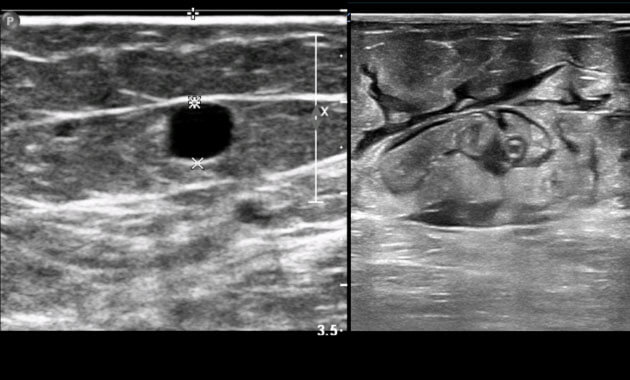

A doctor can usually diagnose varicose veins by simple visual examination. Other diagnostic tests may also be required, such as a an ultrasound examination of the affected extremity.

Radiofrequency ablation (sometimes referred to as RF ablation), is used to treat large veins, such as the great saphenous vein. RF ablation uses heat to treat and close the affected great saphenous vein from the inside.